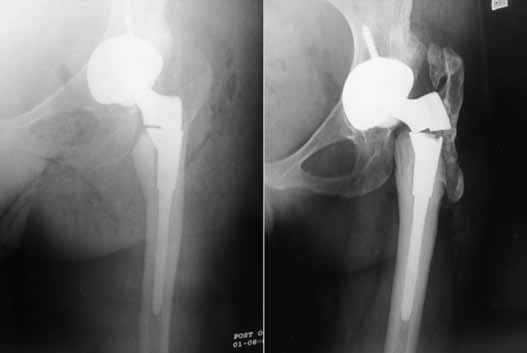

Дислокация бедренного компонента на рентгене.